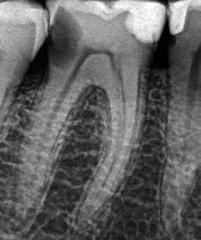

1. a–g. ábrák: A direkt pulpasapkázás lépései. Kiindulási bitewing-felvétel: A meglévő restaurátum közel helyezkedett el a pulpakamrához (a). Kiindulási periapicalis felvétel: Nincs periapicalis elváltozás fennállására utaló jel (b). A pulpaexpozíció (c). A vérzéscsillapítás céljából 20 másodpercen keresztül steril vattagombóccal történő kompressziót követően látható pulpaseb (d). A pulpasapkázás céljából behelyezett anyag, a széli részek tisztázása előtt készült felvétel (e). A röntgenárnyékot nem adó ideiglenes tömés behelyezése után készült felvétel (f). Az első ülés végén a röntgenárnyékot nem adó ideiglenes töméssel ellátott fogról készített röntgenfelvétel (g).

2. ábra: A hat hónapos kontroll alkalmával készített röntgenfelvételen vastag dentinhíd látható a pulpasapkázó anyag alatt.

3. ábra: A hároméves kontroll alkalmával készített röntgenfelvételen megfigyelhető a restaurátum pontos illeszkedése.

A kezelést követően a beteg tünetmentes volt. A kérdéses fog a kontrollvizsgálatok során végzett szenzibilitástesztekre fiziológiás reakciókat adott. A hat hónapos kontroll alkalmával készített röntgenfelvételen a sérülésnek megfelelően széles dentinhidat észleltünk (2. ábra). A restaurátum a hároméves kontroll során is megfelelőnek bizonyult (3. ábra)